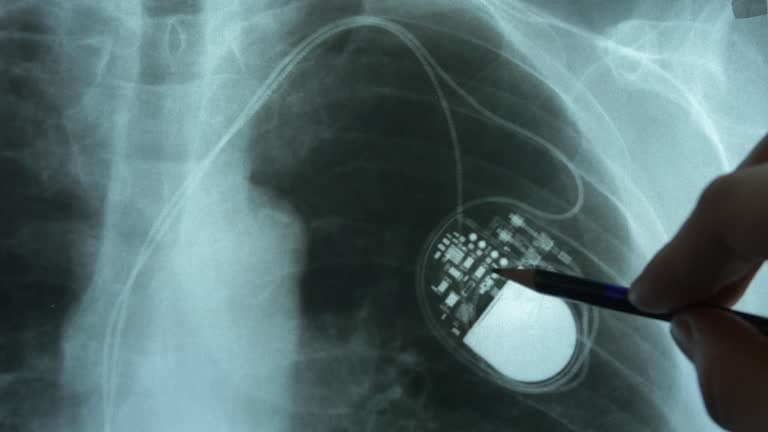

The pacemaker consists of two main components: a pulse generator and one or more leads (wires). The pulse generator is a small, battery-powered unit that produces electrical impulses. It is typically implanted under the skin, just below the collarbone. The leads are thin, flexible wires that extend from the pulse generator to the heart. These leads are threaded through blood vessels and attached to the heart muscle. They transmit the electrical impulses from the pulse generator to the heart, stimulating it to contract at a regular rate.

The implantation of a pacemaker is a minimally invasive procedure performed under local anesthesia. The surgeon makes a small incision near the collarbone and threads the leads through a vein to the heart. The pulse generator is then implanted under the skin, and the leads are connected to it. The entire procedure typically takes a few hours, and most patients can return home the same day or the next.